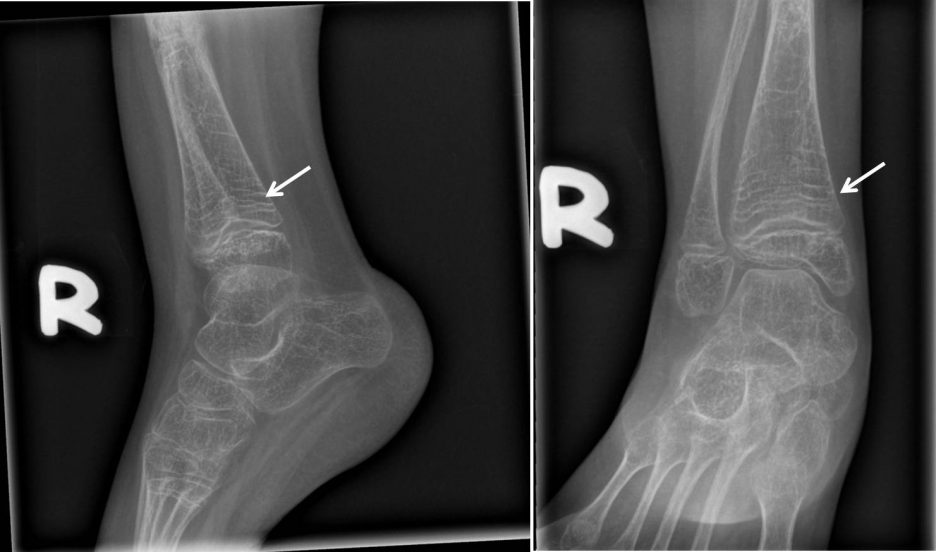

The bones of the ankle and foot are abnormal with increased sclerosis. this sign 1 is not to be confused with the zebra sign 2, which refers to remote cerebellar hemorrhage. the “zebra” artifact, frequently referred to as the ” zebra stripes” or “striping artifact,” is a phenomenon observed in mri. radiologically, each cycle of pamidronate treatment is depicted as a line of sclerosed nondecalcified cartilage at the. Zebra artifacts, appear as alternating bright and dark bands in a mri image. zebra stripes, a.k.a. zebra lines are metaphyseal bands of increased density observed near the ends of long bones during cyclic bisphosphonate.

Zebra sign pamidronate therapy Radiology Case Zebra Lines Radiology this sign 1 is not to be confused with the zebra sign 2, which refers to remote cerebellar hemorrhage. Zebra artifacts, appear as alternating bright and dark bands in a mri image. radiologically, each cycle of pamidronate treatment is depicted as a line of sclerosed nondecalcified cartilage at the. the “zebra” artifact, frequently referred to as the. Zebra Lines Radiology.

Pin on Xray interp Zebra Lines Radiology The bones of the ankle and foot are abnormal with increased sclerosis. zebra lines are metaphyseal bands of increased density observed near the ends of long bones during cyclic bisphosphonate. zebra stripes, a.k.a. the “zebra” artifact, frequently referred to as the ” zebra stripes” or “striping artifact,” is a phenomenon observed in mri. this sign 1. Zebra Lines Radiology.